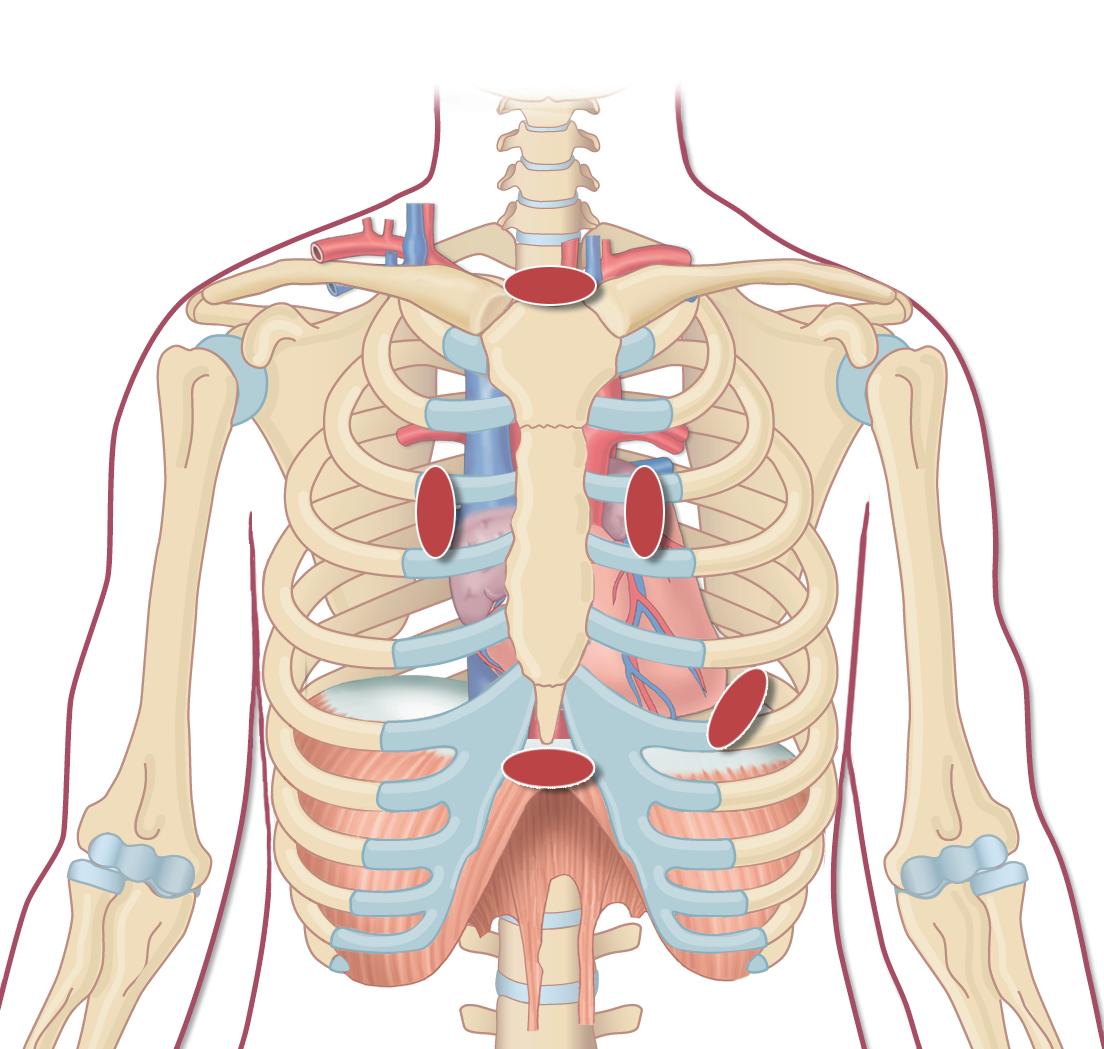

De ulike projeksjonene

I en vanlig transtorakal undersøkelse fremstilles følgende projeksjoner (og i denne rekkefølgen): parasternal langakse, parasternal kortakse, apikal 4-kammer, apikal 5-kammer, apikal 2-kammer, apikal langakse, subkostal og suprasternal projeksjon (figur 2.1).

Suprasternal

Venstre parasternal

Apikal